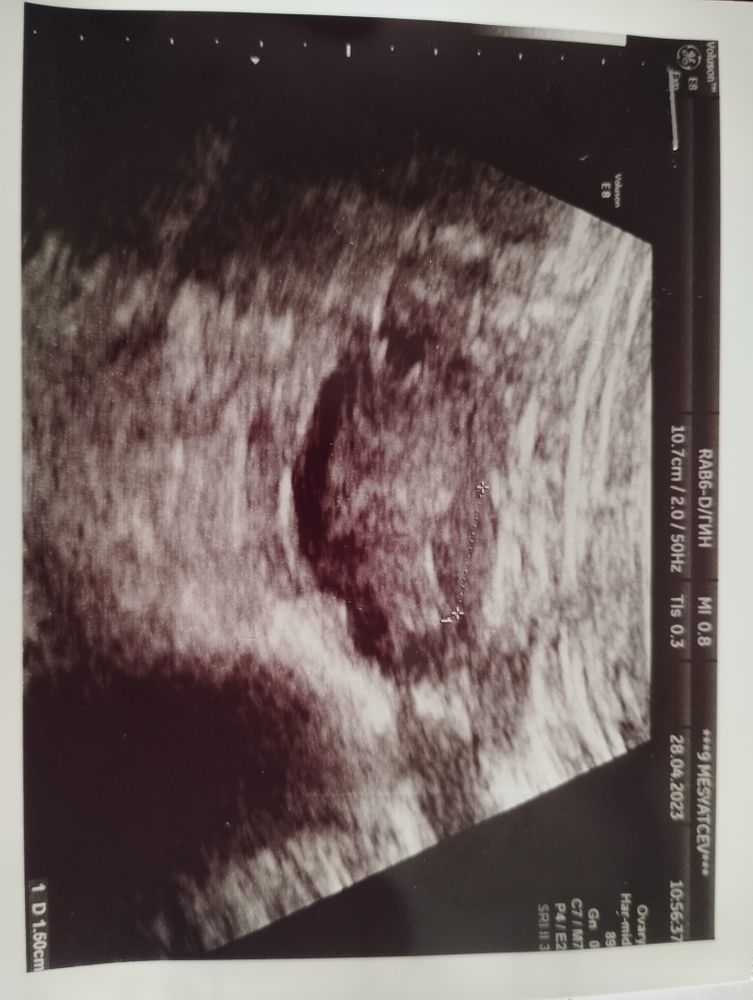

Доброго дня всем!Есть ли эксперты по УЗИ,которые могут подсказать по фото,это доминантный фолликул или просто тень?Никак не укладывается в голове,что 28.04 по УЗИ в левом яичнике нашли ДФ 15 мм(что на фото внизу)Но нашли яичник только трансабдоминальным датчиком,через влагалищный никак не удавалось.И вот пошла я сегодня 04.05 на УЗИ,а мне говорят ,что в левом яичнике не то что ЖТ нет,так ещё и доминантном не пахло.И то ,что увидели неделю назад,это вообще не фолликул может был.Узисты разные.И я сама думаю,ведь доминант он круглый,черный,а это что на фото?Какая то серая лепешка...Никогда такие фолликулы большие не сдувались,овуляция своя бывает,но не регулярно

Татьяна Газизова, это больше похоже на жёлтое тело, но никак не на фолликул

Татьяна Газизова, на фото это не фолликул совсем. И к сожалению фолликулы могут сдуваться

Это точно не доминантный фолликул, скорее жёлтое тело

Виктория, вот я сейчас тоже об этом думаю,но я была на стимуляции летрозолом с 5-9 д.ц. по 1 табл.После была на УЗИ 24 апреля(13 д.ц.)и самый большой фоллик был в левом яичнике-11 мм.Неужели к пятнице так быстро образовалось ЖТ?

Татьяна Газизова, может ещё, как вариант, фолликул лютеинизировался и овуляции просто не было, а он сморщился. Тогда картина становится ясна.